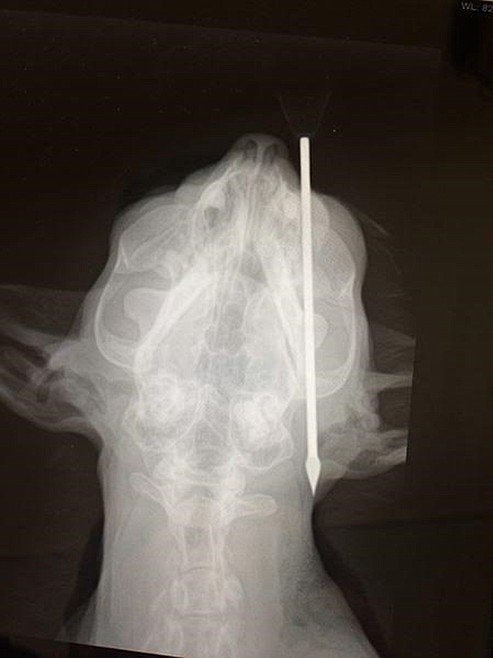

—Courtesy image This X-ray image shows how a 4.5-inch blow dart went into Red’s head.

The 11-year-old tabby short-hair mix owned by Carson Kelley and his girlfriend, Katelyn Halpin, in Coeur d'Alene took a 4.5-inch blowgun dart to the face on Thursday — and amazingly survived.

The dart entered Red's head near an eye at a slight angle.

"It missed his brain by a half a centimeter," Halpin said. "He's one lucky cat."